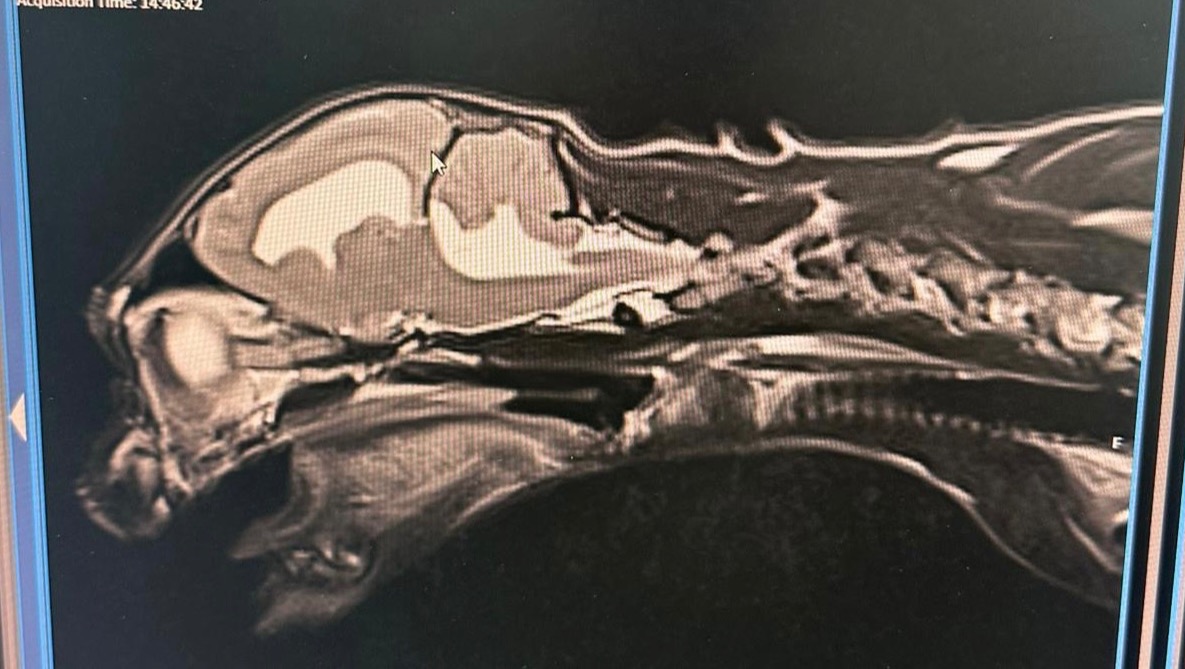

An MRI revealed inflammation of his brain, severe enough that it’s stopping his cerebrospinal fluid from draining. This is putting pressure on his brain, causing it to push past his skull, creating problems for his nervous system, and causing chronic inflammation throughout his body.

They also need to consider the costs for further MRI imaging to check if his condition is improving, and potential surgery to place a shunt to allow his cerebrospinal fluid to drain.